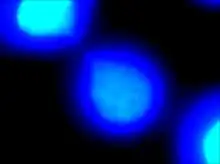

| DAPI staining allows for visualization of deoxyribonucleic acid portions of the two daughter cells. The thin “string-like” DNA connecting them is defined as a chromatin bridge. | |

Chromatin bridges can be viewed utilizing a laboratory technique known as fluorescence microscopy. Fluorescence is the process that involves excitation of a fluorophore (a molecule with the ability to emit fluorescent light in the visible light spectrum) using ultraviolet light. After the fluorophore becomes chemically excited by the presence of UV light, it emits visible light at a specific wavelength, producing different colors. Fluorophores may be added as a molecular tag to different portions of a cell. DAPI is a fluorophore that specifically binds to DNA and fluoresces blue. In addition, immunofluorescence may be used as a laboratory technique to tag cells with specific fluorophores using antibodies, immune proteins created by B lymphocytes. Antibodies are utilized by the immune system in the identification and binding of foreign substances. Tubulin is a monomer of microtubules that compose the cellular cytoskeleton. The antibody anti-tubulin specifically binds to these tubulin monomeric subunits. A fluorophore can be chemically attached to the anti-tubulin antibody, which then fluoresces green. Numerous antibodies may bind to microtubules in order to amplify the fluorescent signal. Fluorescence microscopy allows for the observation of different components of the cell against a dark background for high intensity and specificity.

Chromatin bridges are easiest and most readily visible when observing chromosomes stained with DAPI. DNA bridges appear to be a blue, “string-like” connection between two separated daughter cells. This effect is created when sticky ends of chromosomes remain connected to one another, even after mitosis. A chromatin bridge may also be observed using indirect immunofluorescence, in which anti-tubulin emits a green coloration when bound to microtubules in the presence of UV light. Because microtubules maintain the positions of the chromosomes during mitosis, they appear to be densely pinched between the two dividing, daughter cells. Chromatin bridges can be difficult to locate utilizing fluorescence microscopy, as this phenomenon is not incredibly abundant and tend to appear faint against the dark background.